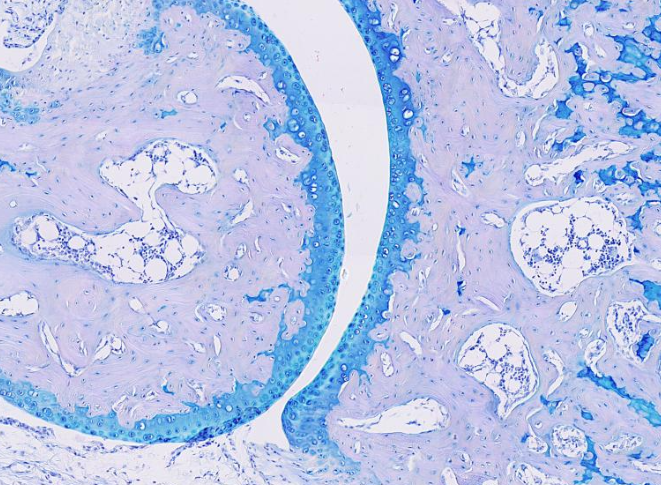

Este tejido es rico en glucosaminoglicanos y proteoglucanos, además de contener colágeno y otras fibras. Selecciona el sitio anatómico donde se puede encontrar el tejido:

Cartílago de articulación (articulación)